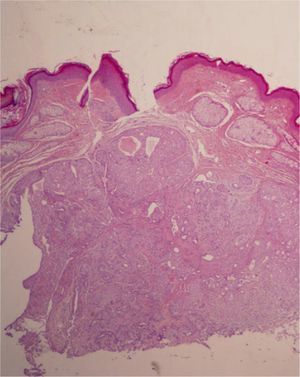

HistopathologyHistopathology revealed a nodular lesion with an expansive growth pattern and well-defined borders (Fig. 2). The lesion consisted of nests of cuboidal epithelial cells without atypia that formed occasional glandular lumina associated with a stroma that was myxoid in some areas (Fig. 3).

Histology reveals well-defined nests of polygonal cells containing tubulo-alveolar and glandular structures within a fibroadipose, chondroid, myxoid, or hyaline stroma. Periodic acid-Schiff and Alcian blue staining is positive.3,5 The eccrine type presents only 1 layer of cuboidal cells with small lumina, while the apocrine type involves tubular, cystic, ramified lumina lined by 2 layers of cells. Staining is usually positive for cytokeratin, S-100, epithelial membrane antigen, vimentin, actin, glial fibrillary acidic protein, and p63.5 The benign form of chondroid syringoma does not present atypia, mitoses, or pleomorphism and does not recur. However, the malignant form, which does not arise from a previously benign lesion,5 is characterized by cytologic atypia, mitoses, poorly defined borders, satellitosis, and necrosis.3–5 Some authors also refer to an atypical form when the data on malignancy are not conclusive.6